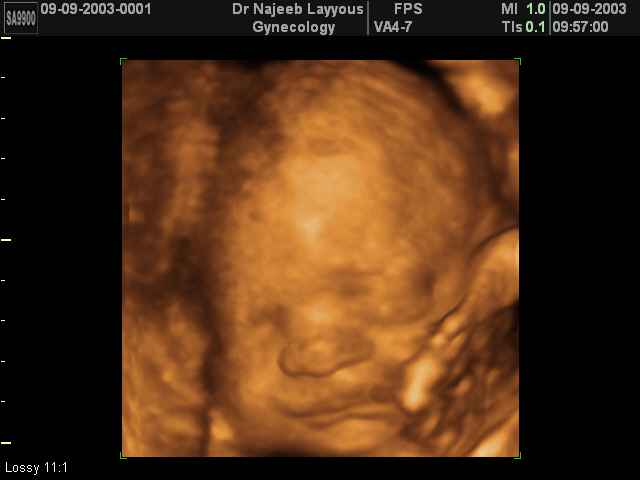

3D Fetal Face Ultrasound Scan Photos